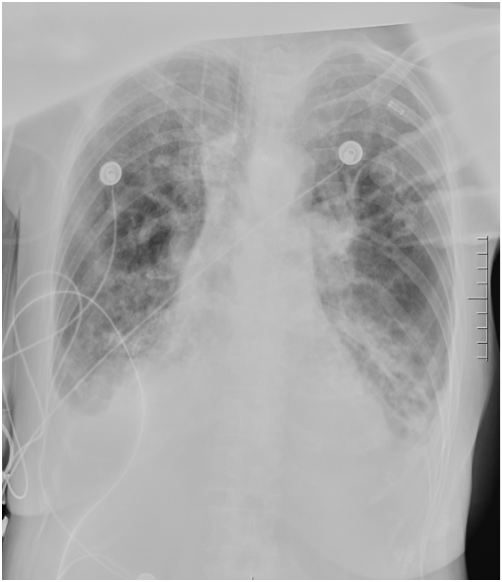

胸部CT:两下肺支气管扩张明显,左下肺大量痰液堵塞(图1)

图1  患者入院后胸部CT